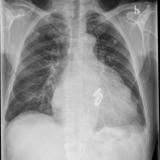

Cardiomegaly, esp RA PA